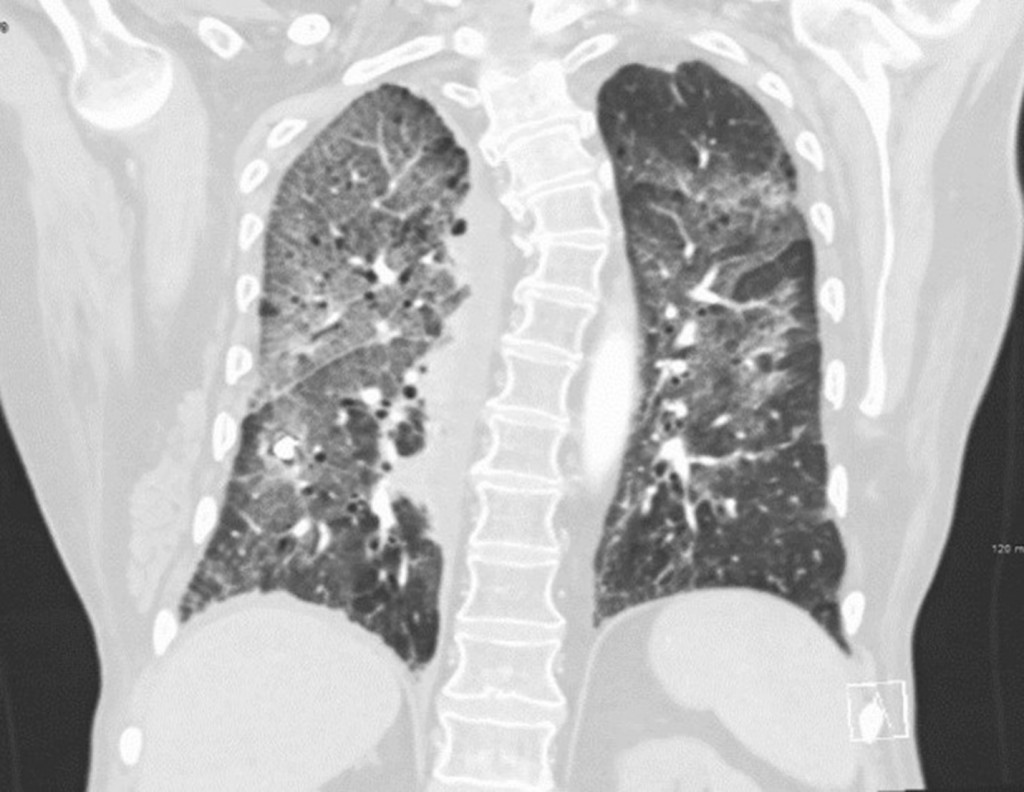

隐源性机化性肺炎(Crytogenic organizing pneumonia COP),是病因不明的肺间质炎症和纤维增生,向肺泡蔓延,导致肺泡逐渐填满蛋白质、成纤维细胞和纤维。症状是干咳、呼吸困难、发烧、全身不舒服。CT可以发现弥漫性实变、玻璃样浸润、弥漫性纤维化。与其它疾病如癌症、结缔组织病相关的,叫继发性机化性肺炎(Secondary organizing pneumonia)。究竟什么引发了这些病理改变不清楚。和其它原因不明的间质性肺炎不同,机化性肺炎肺脏的结构没有被破坏,及时治疗肺脏可能恢复正常。

第12天我接手,只管一天,代别人班。读完逐日志,发现肺科医生计划当天把甲基强的松龙降到40毫克静脉注射,每天两次。查完房,回头再把记录、化验、药物、氧气需要量读了一遍, 把CT翻来覆去看了两遍。 我认为这个病人是COP。 肺科医生上了皮质激素,是正确的措施。 但是剂量不够大,更不应该现在就减量。